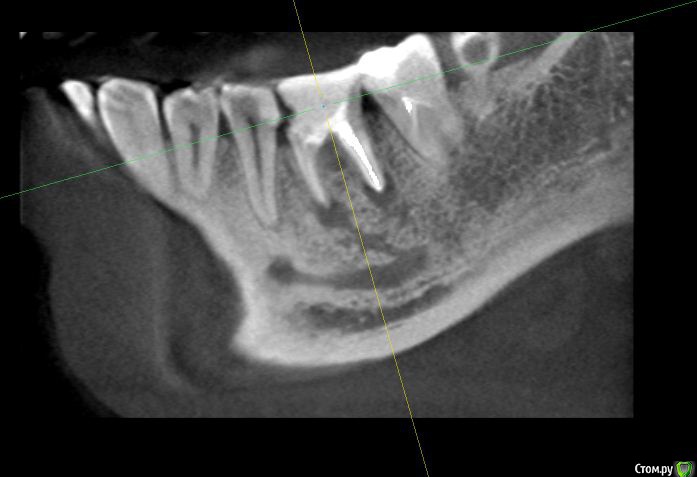

alex_ts Опубликовано 7 ноября, 2016 Поделиться Опубликовано 7 ноября, 2016 (изменено) Здравствуйте. Периодически беспокоит нижняя 6ка, 3 года назад она была на 3/4 разрушена и там стояла "металлическая" черная пломба, от которой зуб приобрел синий оттенок. На мой вопрос что его наверное надо удалять, стоматолог на меня тогда удивленно посмотрела и сказала что корни хорошие и ничего удалять не надо. Тогда же она поставила очень большую пломбу, сказав что это не на долго и так или иначе придется одевать коронку. Сейчас зуб время от времени побаливает и иногда кровит. Сходил в клинику, сделали кт зуба. Врач сказала что варианта 2, либо долго и сложно лечить этот зуб и протезировать, но без гарантии, так как там затемнение в области фуркации, либо удалять и ставить имплант. Что вы порекомендуете в данной ситуации? Спасать зуб или лучше будет избавиться от него? Мч, 24 года Изменено 7 ноября, 2016 пользователем alex_ts Ссылка на комментарий

anvladd Опубликовано 7 ноября, 2016 Поделиться Опубликовано 7 ноября, 2016 Лучше удалить,разрушен между корнями. 2 Ссылка на комментарий

DmitrySH Опубликовано 7 ноября, 2016 Поделиться Опубликовано 7 ноября, 2016 Плохой прогноз для лечения, удалять 2 Ссылка на комментарий